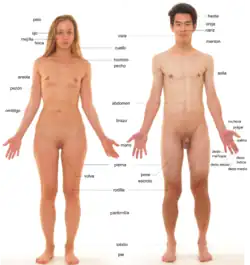

- Anatomía humana: Describe las estructuras morfológicas del cuerpo humano.

Anatomía humana

La anatomía humana tiene muchas similitudes con la de la mayoría de los mamíferos. Para su mejor comprensión se divide en sistemas y aparatos.